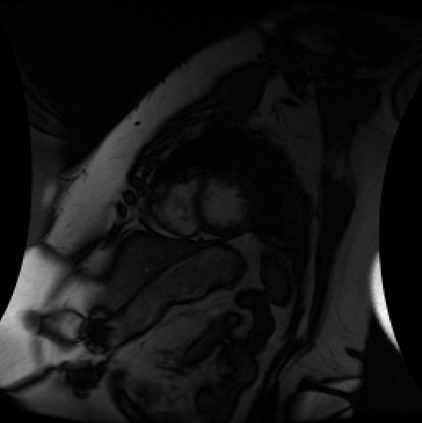

Deep Convolutional Neural Networks (DCNNs) are used extensively in medical image segmentation and hence 3D navigation for robot-assisted Minimally Invasive Surgeries (MISs). However, current DCNNs usually use down sampling layers for increasing the receptive field and gaining abstract semantic information. These down sampling layers decrease the spatial dimension of feature maps, which can be detrimental to image segmentation. Atrous convolution is an alternative for the down sampling layer. It increases the receptive field whilst maintains the spatial dimension of feature maps. In this paper, a method for effective atrous rate setting is proposed to achieve the largest and fully-covered receptive field with a minimum number of atrous convolutional layers. Furthermore, a new and full resolution DCNN - Atrous Convolutional Neural Network (ACNN), which incorporates cascaded atrous II-blocks, residual learning and Instance Normalization (IN). Application results of the proposed ACNN to Magnetic Resonance Imaging (MRI) and Computed Tomography (CT) image segmentation demonstrate that the proposed ACNN can achieve higher segmentation Intersection over Unions (IoUs) to U-Net and Deeplabv3+, but with significantly reduced trainable parameters.